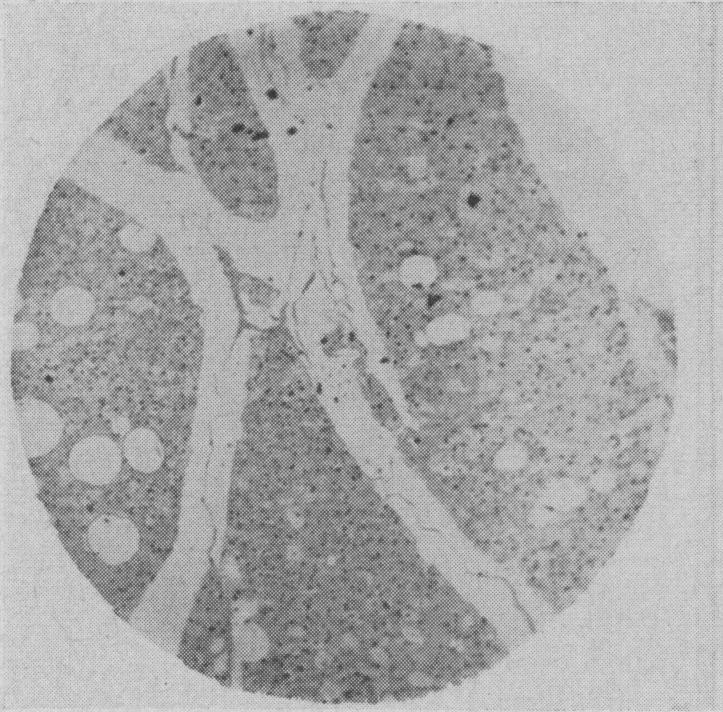

Tumours of brown fat.

Can Med Assoc J. 1954 Nov;71(5):484-5.